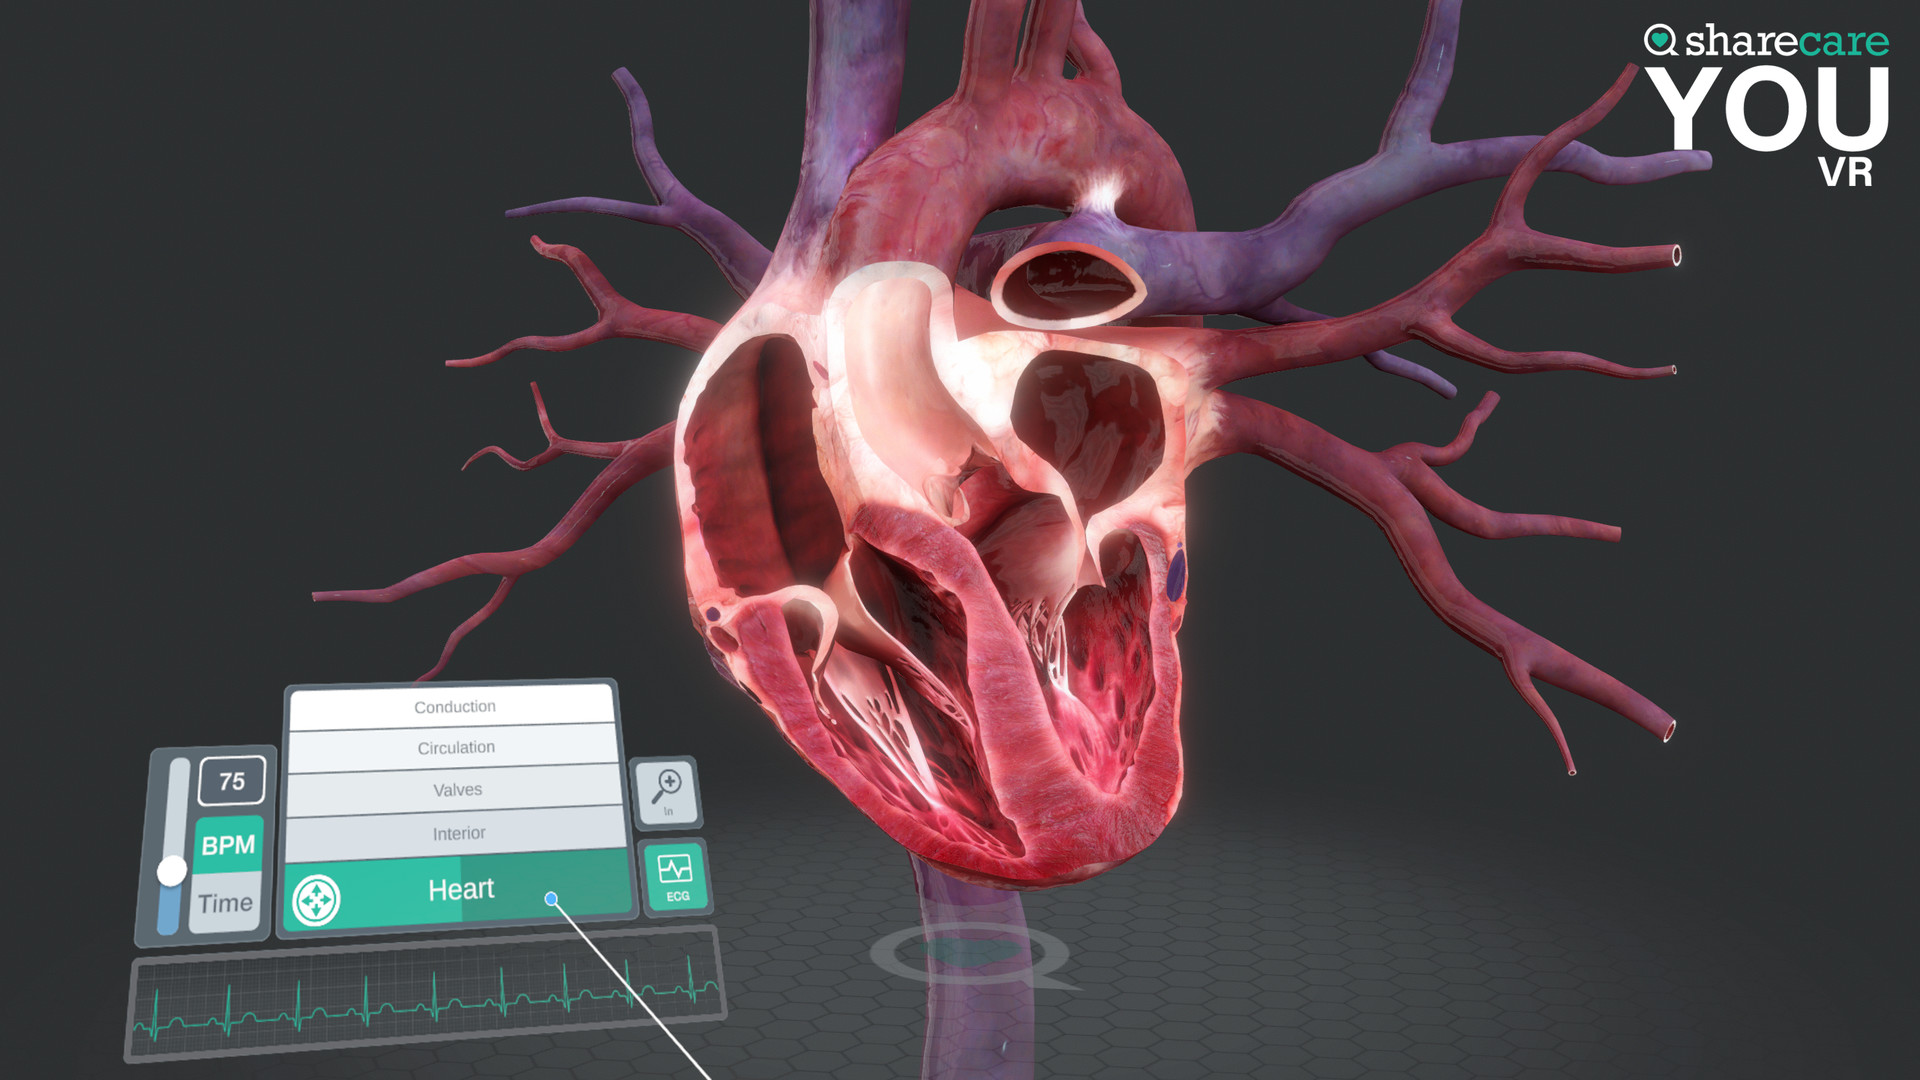

Sharecare YOU是一种完全身临其境的、逼真的人体模拟,让任何人都可以 360 度全方位探索其惊人的细节。

有兴趣了解特定器官吗?只需单击一个按钮,即可进入内部,想象其自然功能,并深入探索。想了解更多吗?查看沿途的许多标签和标签,以获得更多信息和洞察力。轻松定制您以更好地了解生理学和模拟疾病。您甚至可以将我们的头像个性化为虚拟的您——您的健康、您的状况。这真的是关于你的。

- 你的内容 – 一个包含 40 多个不同场景的扩展库供探索,包括解剖学、生理学、条件和治疗

- 具有独特交互式控件的完全更新的用户界面